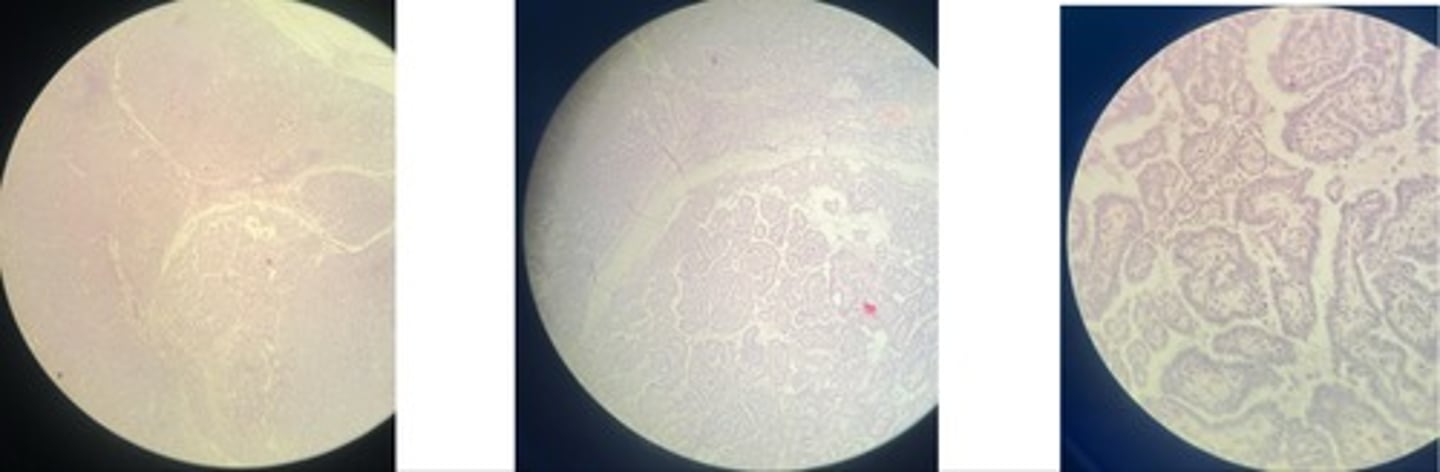

Hepatic coccidiosis … intracell parasites

- dilated bile ducts

- hyperplasia of biliary epi => papillary projections

- oocysts in lumen + inflam cells

- atrophy + degen

Hepatic echinococcus

- cystic structure lined with chitin mem

- may have protoscolices (parasite larvae)

- liver parenchyma => atrophy, fatty degen, necrosis, haemorrhage

- infiltrate cells: macrophages, epitheliod cells and giant cells

Hepatic fascioliasis

- coag. necrosis + haemorrhages

- hemosiderin pigments + inflam cells

- fibrosis @ portal area

- prolif of biliary ducts

- scar formation in migration pathway